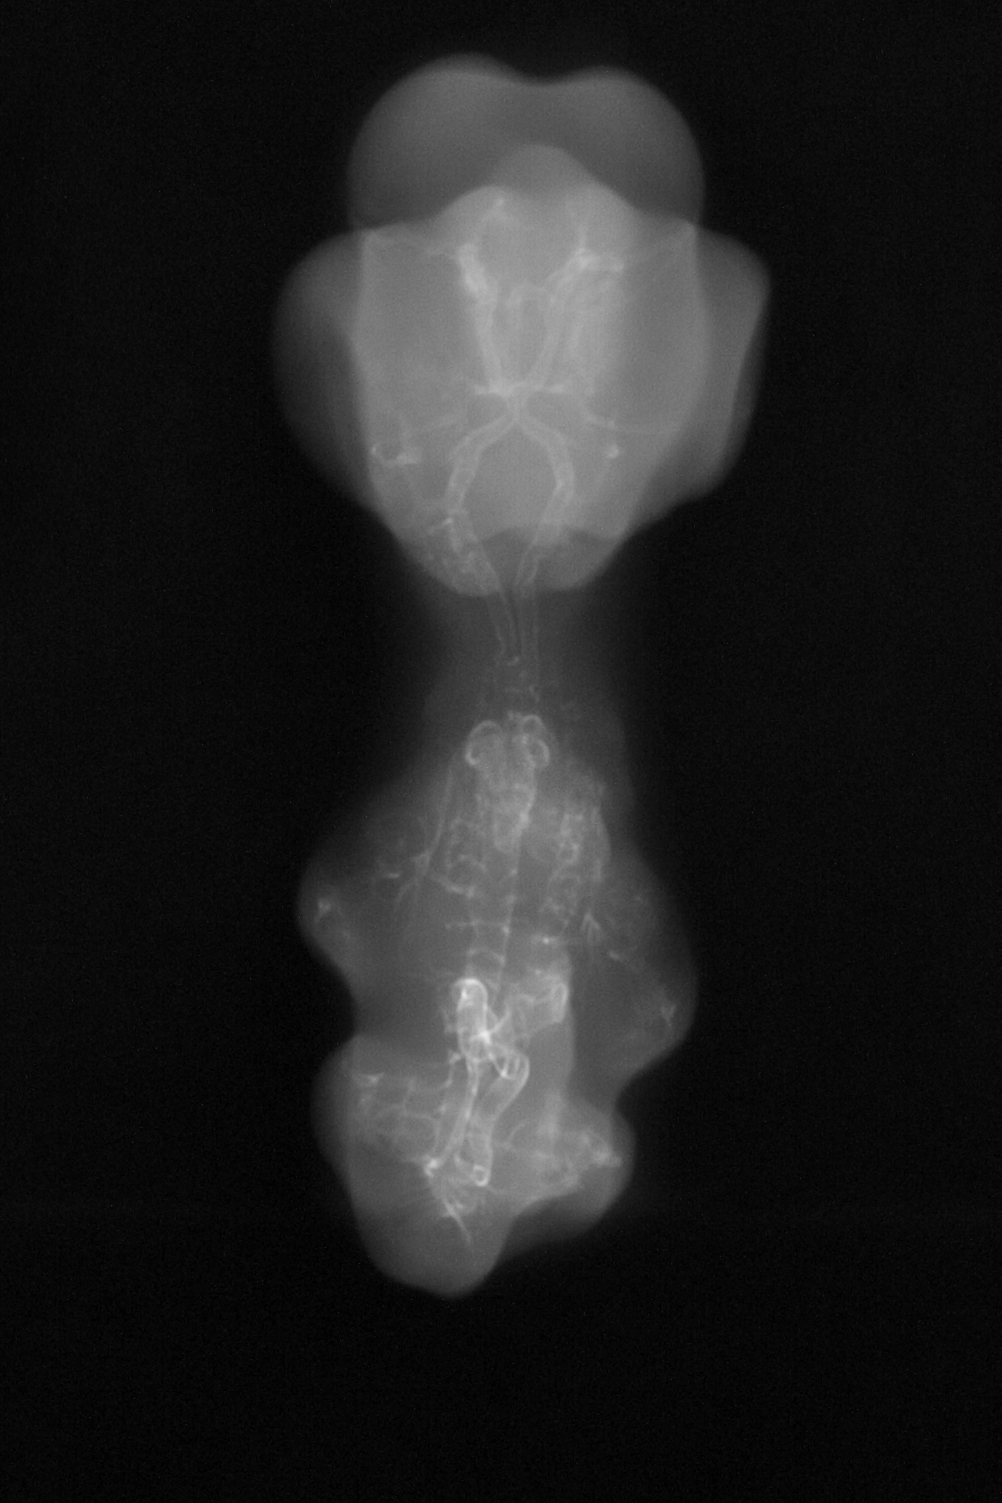

X-Ray Micrographs